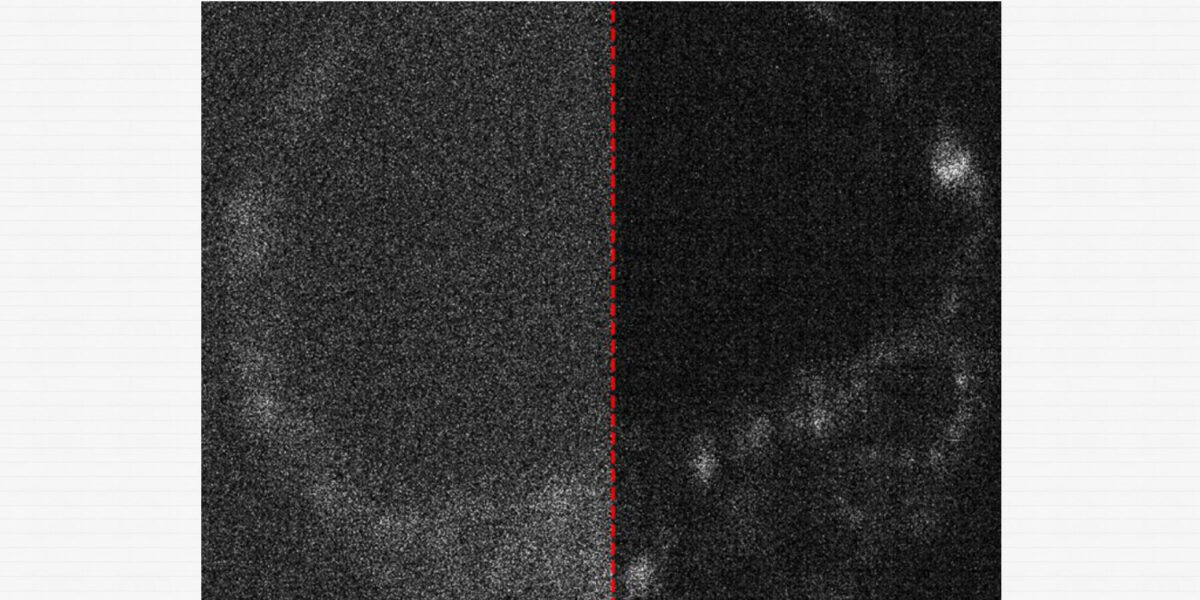

Bild eines lebenden Mausembryos mit und ohne optimierte Aufnahme durch eine Quantenkamera

Bild eines lebenden Mausembryos mit und ohne optimierte Aufnahme durch eine Quantenkamera.

Ein weiterer Aspekt der Forschung ist die Optimierung der Bildqualität. Das Team entwickelte Methoden, um verschiedene Kameras miteinander zu vergleichen und deren Leistungsfähigkeit in der biologischen Bildgebung zu bewerten. Zusätzlich wurden künstliche Intelligenz (KI)-Algorithmen eingesetzt, um Bildrauschen zu reduzieren. Laut Peterkovic geht die Arbeit weit über das reine Einsetzen der Kamera ins Mikroskop hinaus: „Wir haben untersucht, wie KI genutzt werden kann, um Störgeräusche aus den aufgenommenen Bildern zu entfernen, die entstehen, wenn die Kamera Schwierigkeiten hat, genügend Licht einzufangen.“